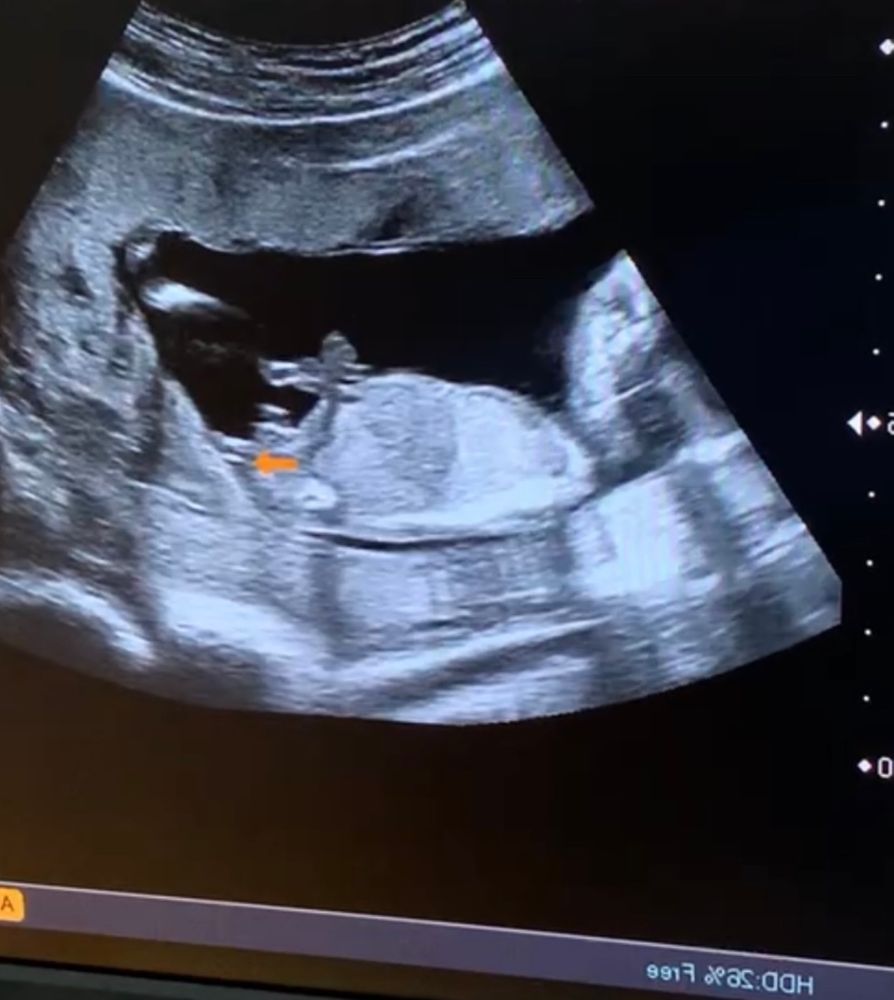

Узистка, как и мы, может только предположить на данном сроке)

Чашка утреннего кофе, я и сама вижу мальчика, просто мальчик уже есть, так хотелось девочку🤣